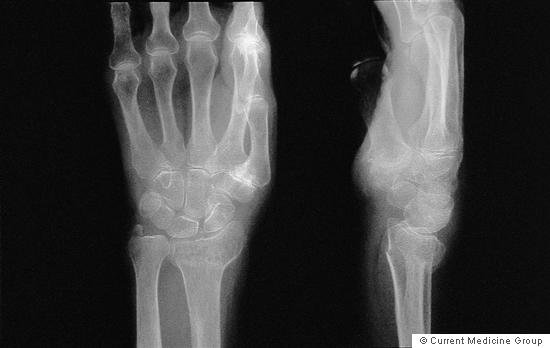

Q3

What sort of fracture is this?

Image source

Greenstick/ non-displaced fracture of the 5th distal metatarsal

The metatarsal of th elittle finger, a little hard to tell which type of fracture it is at that resolution